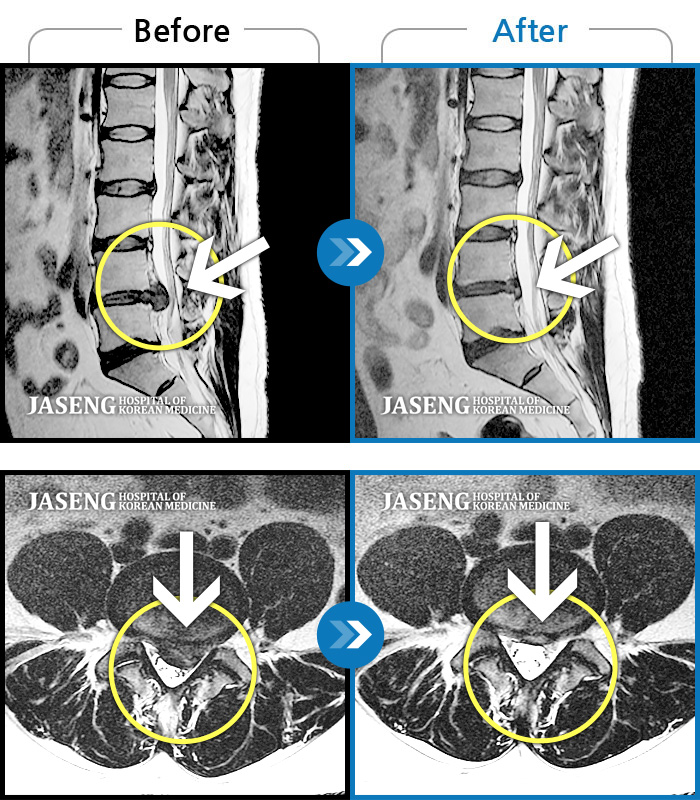

MRI 치료사례

허리 및 왼쪽 하지 통증 및 저림